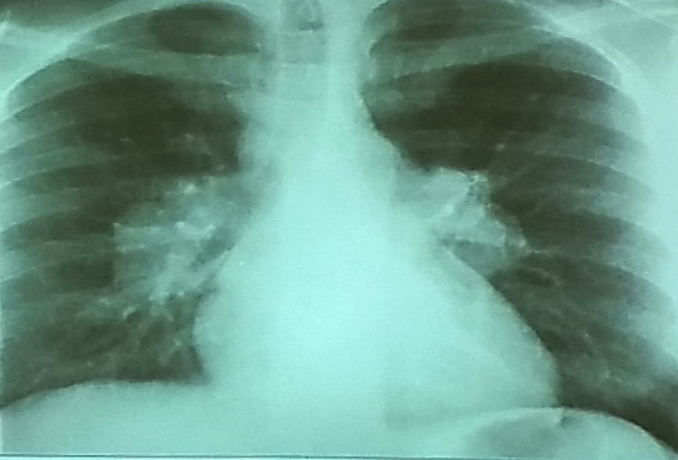

This patient presented with cough, fever, rusty sputum?

What is radiological abnormality present?

right lung show cavity that contain air fluid level (Post pneumonic abscess) Z -

Name 2 causes for this condition?

a. --------TB--------

b. --------pneumonia-------- C. --------Lung Access /Mass--------